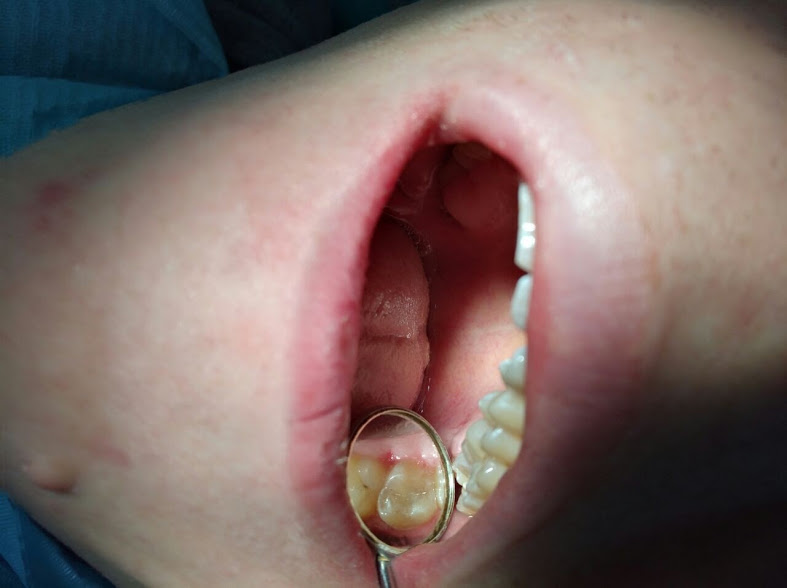

IMG-20170124-WA0008.jpg

| Владелец: | Роман Абдуллахович Салех |